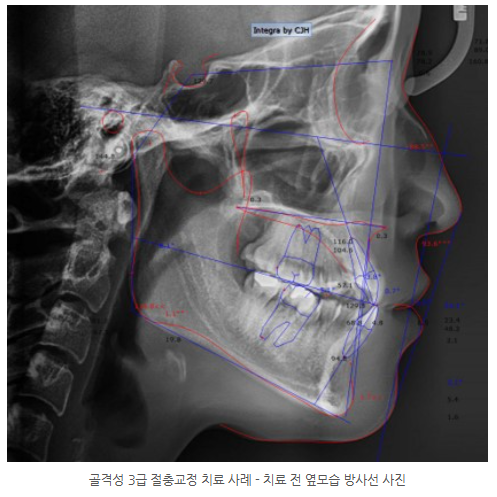

양악수술을 권유받았던 20세 여성 골격성 3급 부정교합 환자.

발치 교정과 미니스크류를 이용한 비수술 절충교정으로 기능과 심미를 개선한 실제 치료 사례를 소개합니다.

초진 시 진단 소견

환자는 20세 여성으로, 다음과 같은 특징을 보였습니다.

골격성 3급 부정교합

안면 비대칭

양측 3급 구치관계

전치부 및 구치부 반대교합

총생(Crowding)

상·하악 중심선 불일치

정밀 검사 및 치료 계획

골격적 한계는 존재하나

이에 따라 수술 없이 교정 치료를 계획하였습니다.